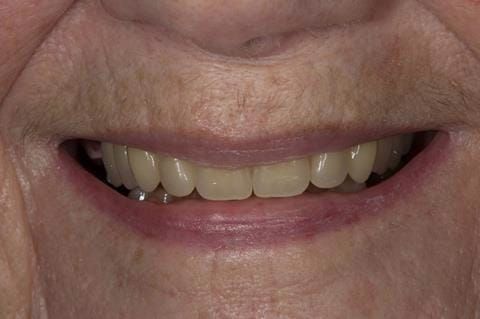

The 'gasket' or 'window' denture - provision of a maxillary cobalt chromium based partial denture

Following consultation and second discussion appointment the patient chose to have option 2 namely, a window denture - maxillary cobalt chromium based partial denture. The clinical situation and treatment process is shown in detail below with photographs. The patient was successfully rehabilitated with this and her quality of life considerably improved. The clinical work was provided by Finlay and the technical work by Rowan.